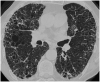

Sarcoidosis is a heterogeneous disease, which can affect virtually every body organ, even though lungs and intra thoracic lymph nodes are almost universally affected. The presence of noncaseating granulomas is the histopathological hallmark of the disease, and clinical picture depends on the organs affected. Data about interaction between sarcoidosis and comorbidities, such as cardiovascular and pulmonary diseases, autoimmune disorders, malignancy and drug-related adverse events are limited. Several lung conditions can be associated with sarcoidosis, such as pulmonary hypertension and fibrosis, making it difficult sometimes the differentiation between complications and distinctive pathologies. Their coexistence may complicate the diagnosis of sarcoidosis and contribute to the highly variable and unpredictable natural history, particularly if several diseases are recognised. A thorough assessment of specific disorders that can be associated with sarcoidosis should always be carried out, and future studies will need to evaluate sarcoidosis not only as a single disorder, but also in the light of possible concomitant conditions.Key messagesComorbidities in sarcoidosis are common, especially cardiovascular and pulmonary diseases.In the diagnostic workup, a distinction must be made between sarcoidosis-related complaints and complaints caused by other separate disorders. It can be very difficult to distinguish between complications of sarcoidosis and other concomitant conditions.The coexistence of multiple conditions may complicate the diagnosis of sarcoidosis, affect its natural course and response to treatment.